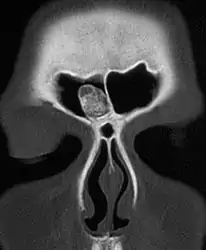

| CT scan showing an osteoma growing on inside of skull bone | |

Medical imaging such as X-ray, CT scan and MRI show dense, clearly defined, round white tumors attached to bone.[1] They may be diagnosed when having medical imaging for another reason.[3] Osteomas of the paranasal sinuses and skull base can be diagnosed using CT-scan without intravenous contrast, allowing its size and relation to nearby important structures to be assessed.[3] A biopsy is not usually required.[3]

CT-scan skull: Osteoma of the frontal sinus